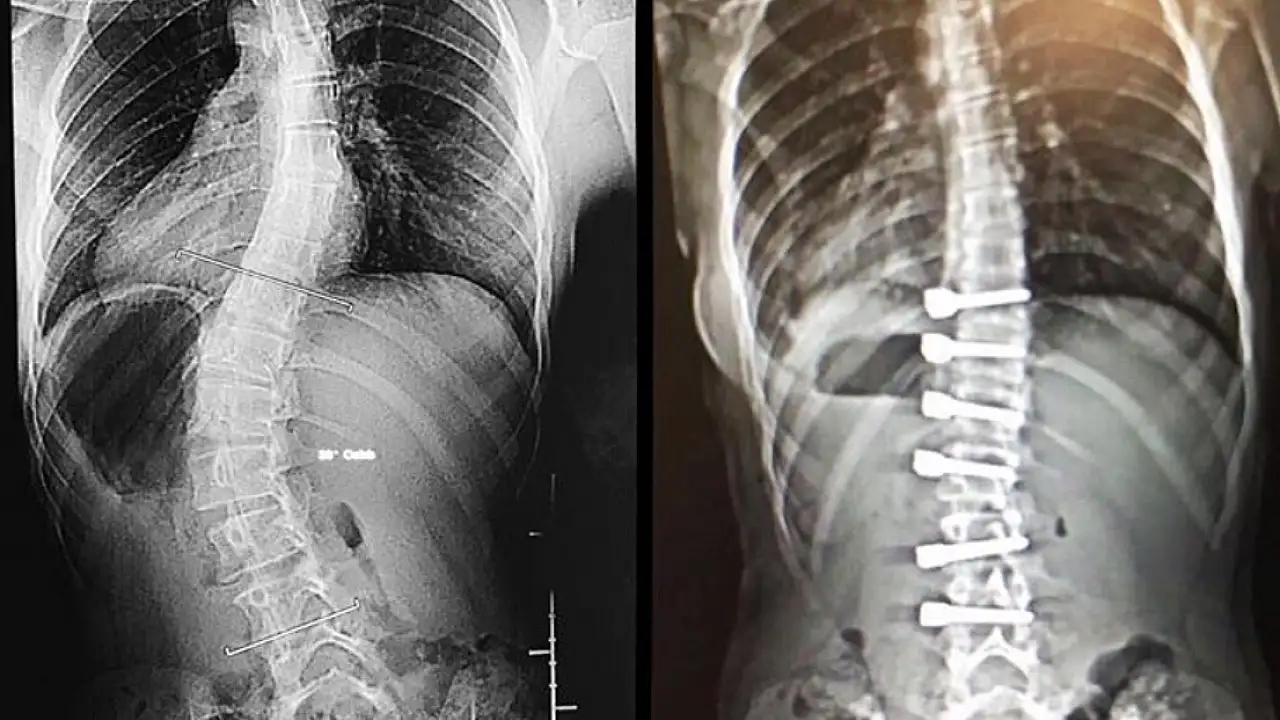

Skolyozda görülen çocuktaki hafif değişikliklerin aile üyesi, yakın bir arkadaş ya da öğretmen tarafından fark edilebileceğini vurgulayan Dr. Ulaş, bu durumda mümkün olduğunca hızlı bir şekilde bir hekime başvurulması gerektiğine dikkat çekti. Skolyoz cerrahisinde amacın eğilmiş omurları düzgün bir şekilde dizip birbirine kaynatmak olduğunu dile getiren Ulaş, "Kaynama sonrasında bu bölge tek bir kemik (omur) gibi hareket eder. Genelde 45-50 derecenin üzerinde olan eğrilikler ergenlik bitip büyüme tamamlansa bile ilerlemeye devam eder. İlerleme sırtta ve belde estetik olarak kötü bir görüntü oluşturduğu gibi akciğer fonksiyonunu da bozabilir. Bu durumda skolyoz cerrahisi yapan çoğu doktor skolyoz eğriliğini azaltmak ya da artmasını engellemek için cerrahi tedaviyi tercih eder. Günümüz teknolojisi skolyoz cerrahlarının eğrilikleri düzeltebilme yeteneklerini artırmıştır. Böylece estetik olarak düzgün bir görüntü elde edilebilir. Eğrilmiş omurların birbirine kaynatıldığı füzyon ameliyatı, skolyoz eğriliğinin artmasını engellemekte çok başarılıdır" ifadelerini kullandı.

“Skolyoz eğriliği ne kadar esnekse o kadar çok düzelir”

Ameliyattan önce özel eğilmeli ya da traksiyon filmi denilen özel röntgen filmleriyle skolyoz eğriliğinin ne düzeyde esnek olduğunun anlaşılmaya çalışıldığını vurgulayan Dr. Ulaş şunları söyledi: "Ameliyatı yapacak olan cerrah bu filmlerle ölçüm yaparak esneklik hakkında fikir sahibi olur. Skolyoz eğriliği ne kadar esnekse, o kadar çok düzelme elde edilir. Skolyoz ameliyatından sonra iz kalmasını engellemek için cilt estetik dikiş kullanılarak dikilir. İz oluşumunu engelleyici kremlerin kullanılması ve ilk yıl güneşe çıkarken kesi hattının üzerinin örtülmesi kullanılan diğer önlemlerdir. Skolyoz ameliyatı, omurganın tekrardan pozisyon verildiği, kasların yerlerinin değiştiği büyük bir ameliyattır. Genelde ameliyat sonrası ilk günlerde ağrı daha fazla olur. Çoğu hasta ağrısı üçüncü günden sonra azalarak hastaneden taburcu olur. Daha sonra aşamalı olarak ağrıları azalır ve genelde 2 ya da 4 hafta sonra okul çağındaki çocuklar okula gidebilirler. Hastalar ameliyat sonrası ikinci günde ayağa kaldırılıp yürütülürler."